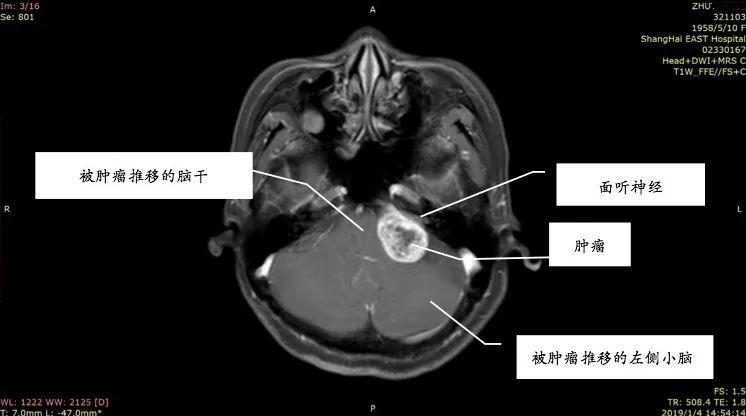

姚先生打电话时总听不清对方讲话,右边耳朵像有蜜蜂在飞,发出嗡嗡的声音。起初并没太在意,以为是工作繁忙劳累或情绪紧张,休息一会儿也就好了。前段时间他感觉耳鸣越来越厉害,并且还出现听力下降、失眠等症状,到医院做了头部的核磁共振增强扫描,发现他患上了听神经瘤。

听神经瘤是指起源于听神经鞘的肿瘤,为良性肿瘤,确切的称谓应是听神经鞘瘤,是常见颅内肿瘤之一。事实上,三分之二以上的人都出现过耳鸣的现象。那么,普通的耳鸣、脑中风的耳鸣与听神经瘤的耳鸣又有何区别呢?

主要是单侧耳鸣,且音调较高,类似蝉鸣声、蟋蟀声,或者金属磨擦声。随着肿瘤越来越大,就可能压迫到周围神经,还也可能出现面部麻木、面肌痉挛、感觉异常、头晕,甚至走路不稳、瘫痪等类似脑中风的症状,且各项症状持续加重没有缓解。

据统计,临床上57%的听神经瘤患者会出现耳鸣等症状,其中26%的患者表现为突发性耳聋。随着肿瘤的生长,患者可能出现听力下降,甚至完全消失。但也不用太恐慌,听神经瘤只要及时接受科学治疗,并不会对患者造成严重危害。只要能够及时手术,切除肿瘤,患者多数可以获得较好的预后,并且听力有可能恢复。